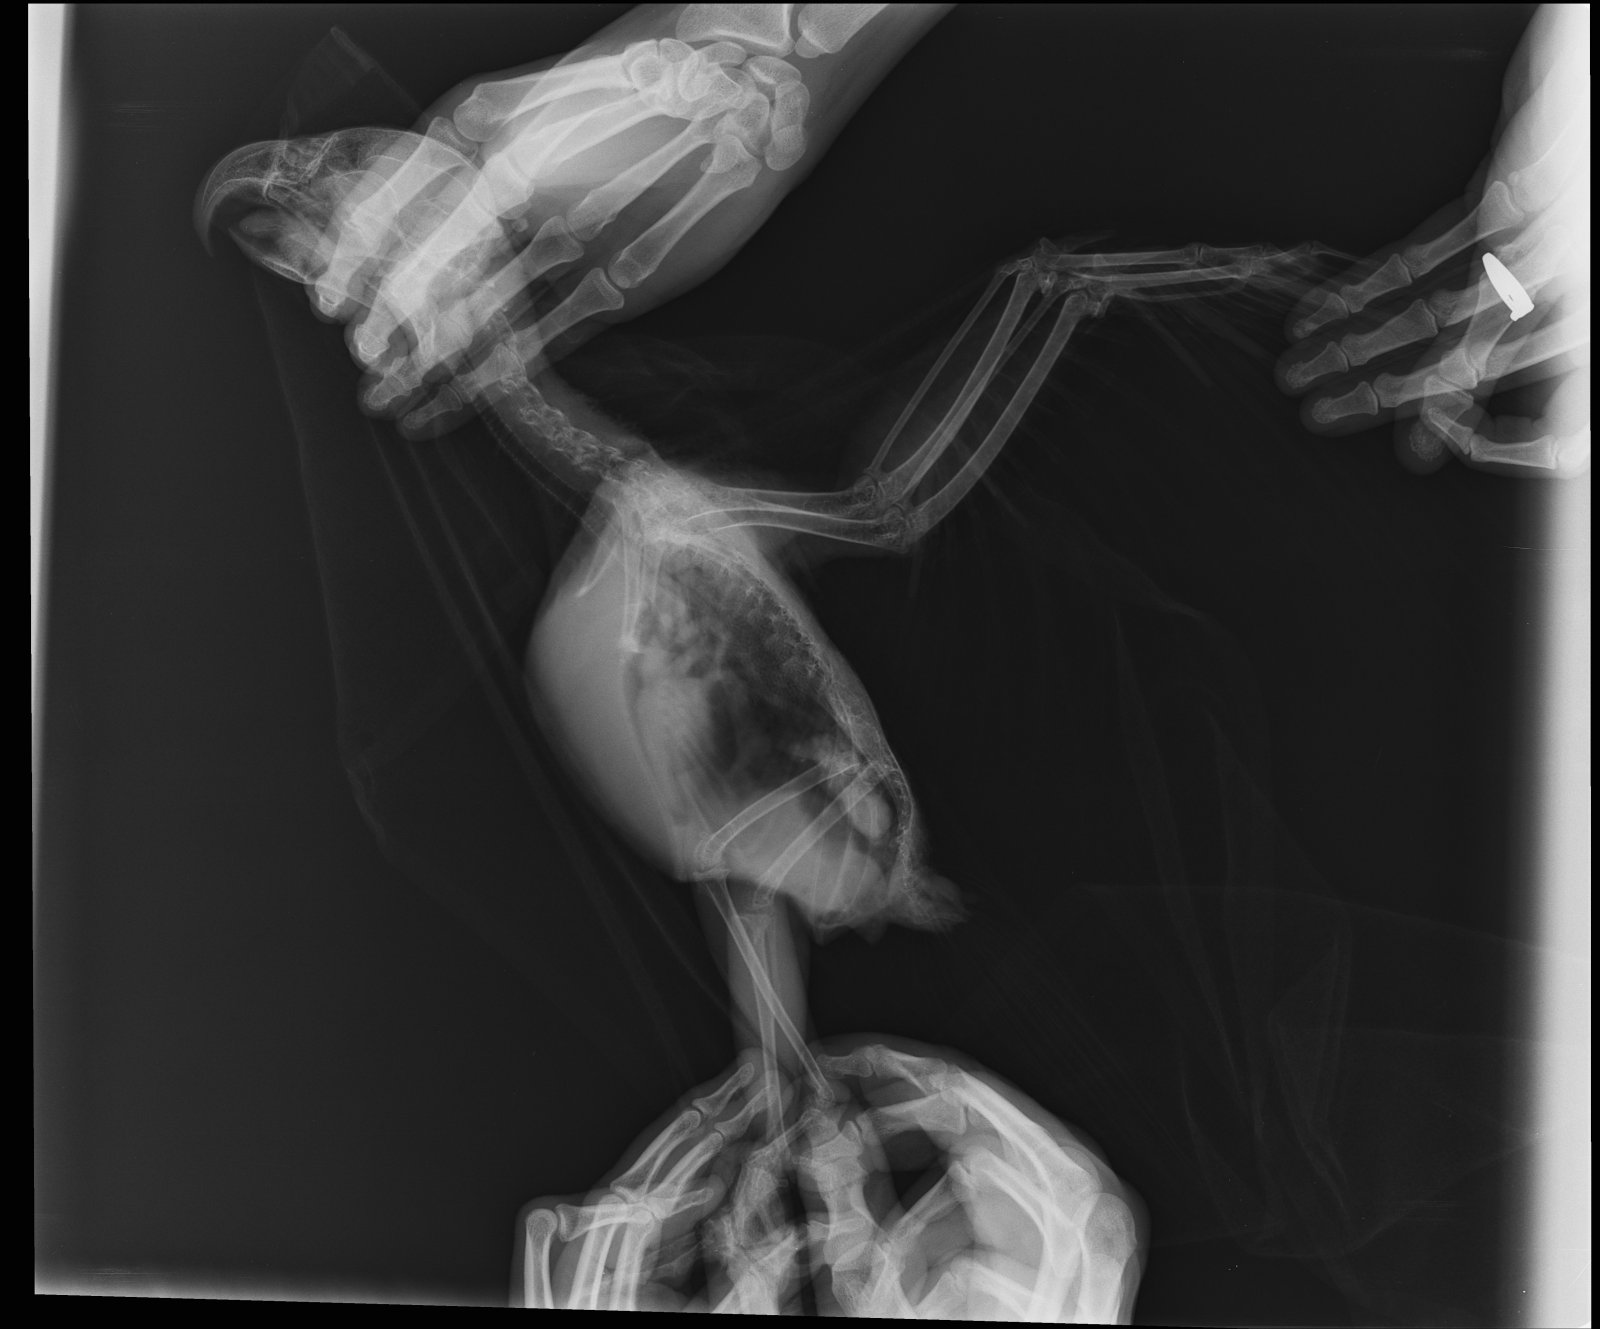

11 декабря сдали анализы. Результаты анализов прикрепила к данному сообщению, а также рентген.

Рентген: очаговые затемнения в легких, затемнен правый брюшной воздушный мешок

Кардтомегалия: увеличен железистый желудок

Диагноз: бронхопневмония, аэросаккулит, кардиопатия